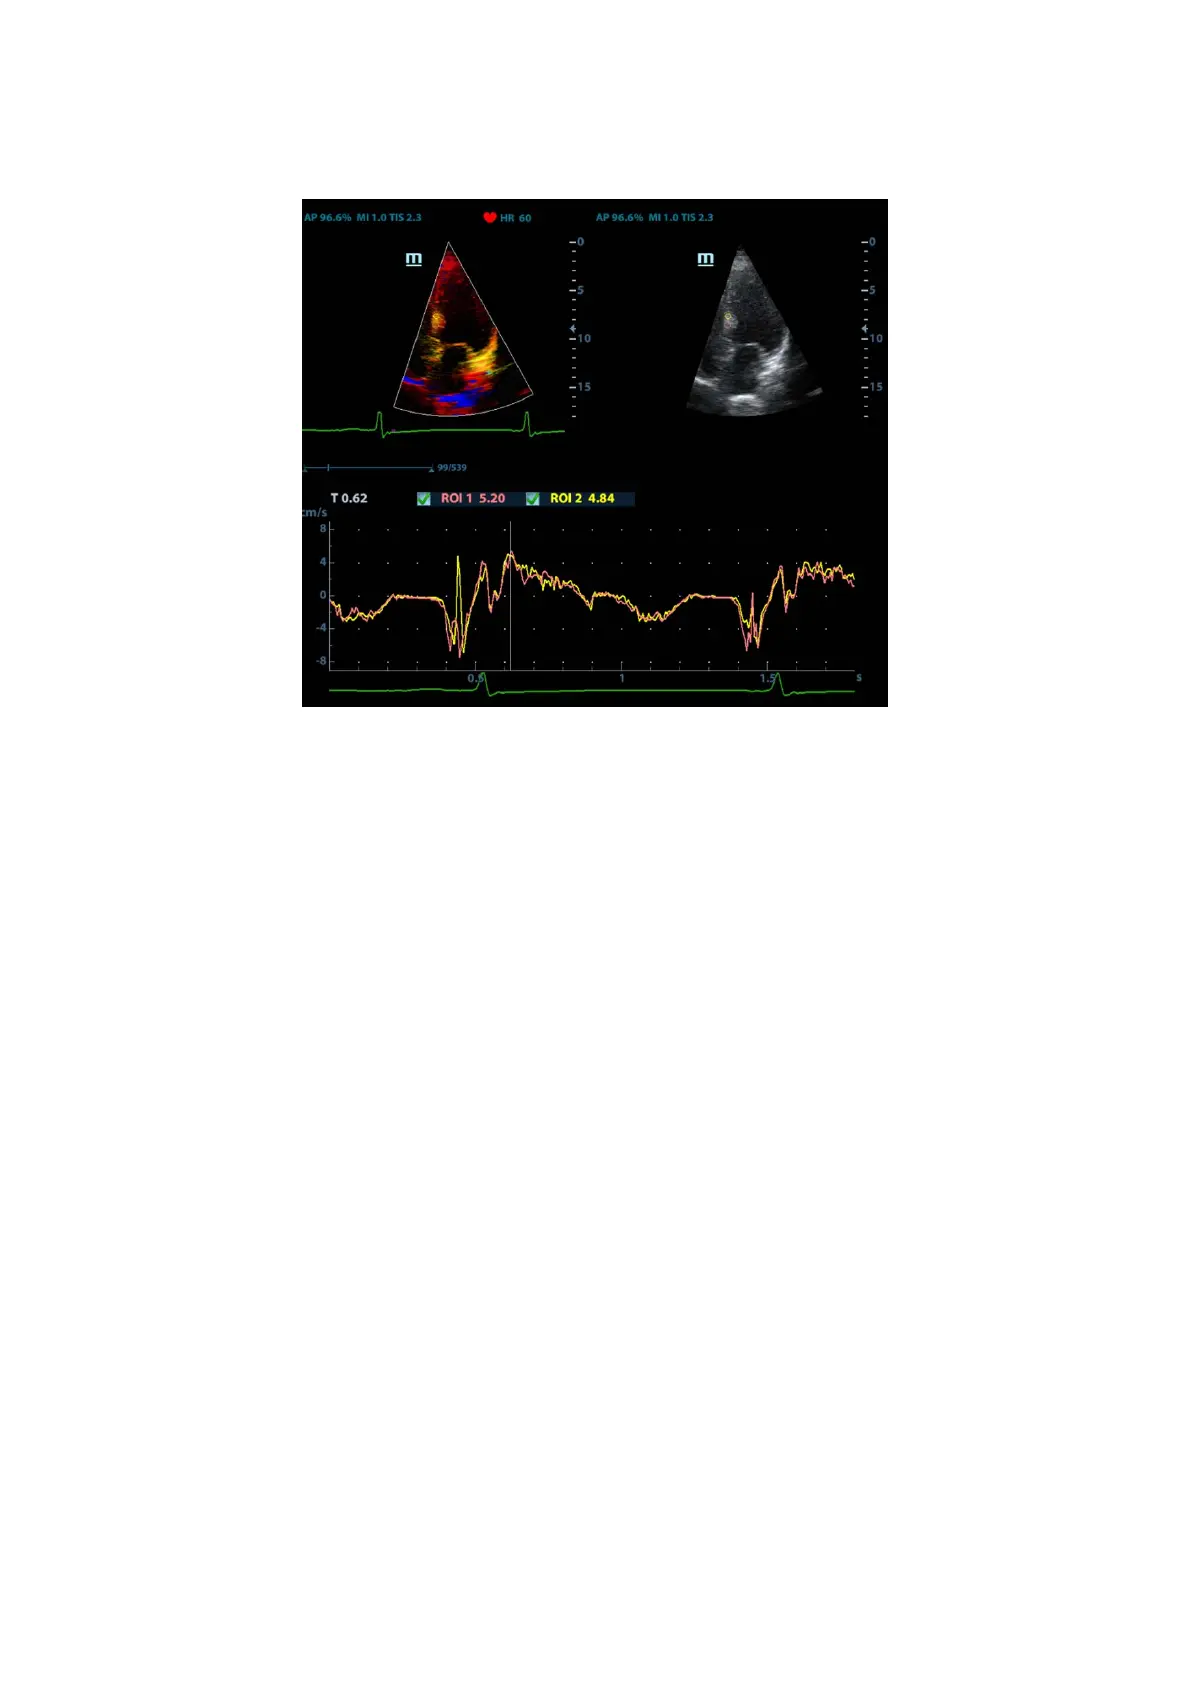

5.9.4.1 TDI QA Screen Description

TDI QA Screen

1 - TVI Cineloop window

Sample area: indicates the sampling position of the analysis curve. The sample area is

color-coded, 8 (maximum) sample areas can be indicated.

2 - B Cineloop window

3 - Displays the analysis curve

z The Y-axis represents the speed (unit: cm/s). [In the Strain Rate – Time curve,

the Y-axis represents the strain (%). In the Strain – Time curve, the Y-axis

represents the strain rate (1/s).]

z The X-axis represents the time (unit: s).

z Frame marker: a white line perpendicular to the X-axis which can be moved

horizontally left to right (and right to left) by rolling the trackball.

z Click the checkbox beside the ROI to set whether to hide or display the QA curve.

z You can get the current X/Y-axis value by moving the cursor onto one point on

the curve. If you press <Set> now, the frame marker will move to that spot.

4 - Displays the ECG trace (no ECG trace displayed here).